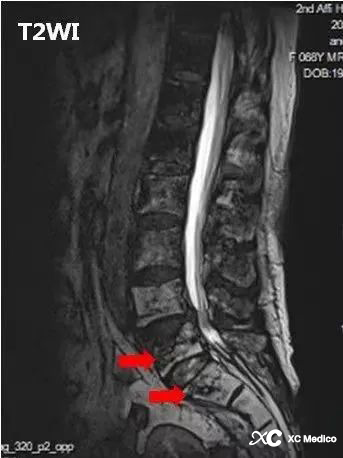

Hnisavá spinální diskitida (PS) je obvykle způsobena hematogenně diseminovanou infekcí, přičemž nejčastějším patogenem je Staphylococcus aureus, nejčastěji postihující bederní páteř, a rentgenové snímky postrádající specificitu a citlivost v časných stádiích onemocnění. Enhanced MRI je metodou volby pro časnou diagnostiku infekcí páteře; MRI demonstruje edém kostní dřeně a zesílení obratlových těl, meziobratlových plotének, epidurálního prostoru a/nebo okolních měkkých tkání s nebo bez tvorby abscesů lokalizovaných primárně v blízkosti obratlových koncových plotének.

Na MRI typická t1 intenzita nízkého signálu a vysoká intenzita signálu sekvencí citlivých na tekutiny zahrnuje přední tělo obratle a může se rozšířit přes subligamentózní dráhu k dalším obratlům, obecně bez zapojení ploténky.